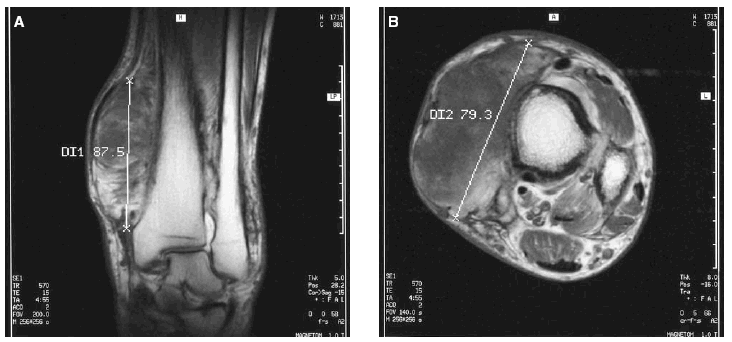

En la analítica sanguínea no se observaron alteraciones bioquímicas ni en el hemograma. Los niveles séricos de testosterona, cortisol, tirotropina, prolactina, lutropina, folitropina y hormona del crecimiento se hallaron dentro de los valores de referencia. El examen histopatológico de una biopsia «en sacabocados» de la lesión violácea del tobillo izquierdo puso de manifiesto una dermatitis de estasis. En el estudio mediante resonancia magnética (RM) de las extremidades inferiores se observó un engrosamiento irregular de la cortical con algunas imágenes de espiculación y con un ensanchamiento metafisario en ambas piernas. La afectación de partes blandas era bilateral, localizada en el tercio distal, más prominente en el lado izquierdo y consistía en una proliferación seudotumoral del tejido adiposo que se infiltraba entre los músculos hasta alcanzar planos yuxtaarticulares asociado a cambios de fibrosis (fig. 6). Se realizó una tomografía computarizada (TC) toracoabdominal que fue normal y que descartó patología pleuropulmonar, hepática y gastrointestinal.

Fig. 6A y B.--Proliferación seudotumoral del tejido adiposo que se infiltra entre los músculos asociado a cambios de fibrosis en el estudio mediante RM.